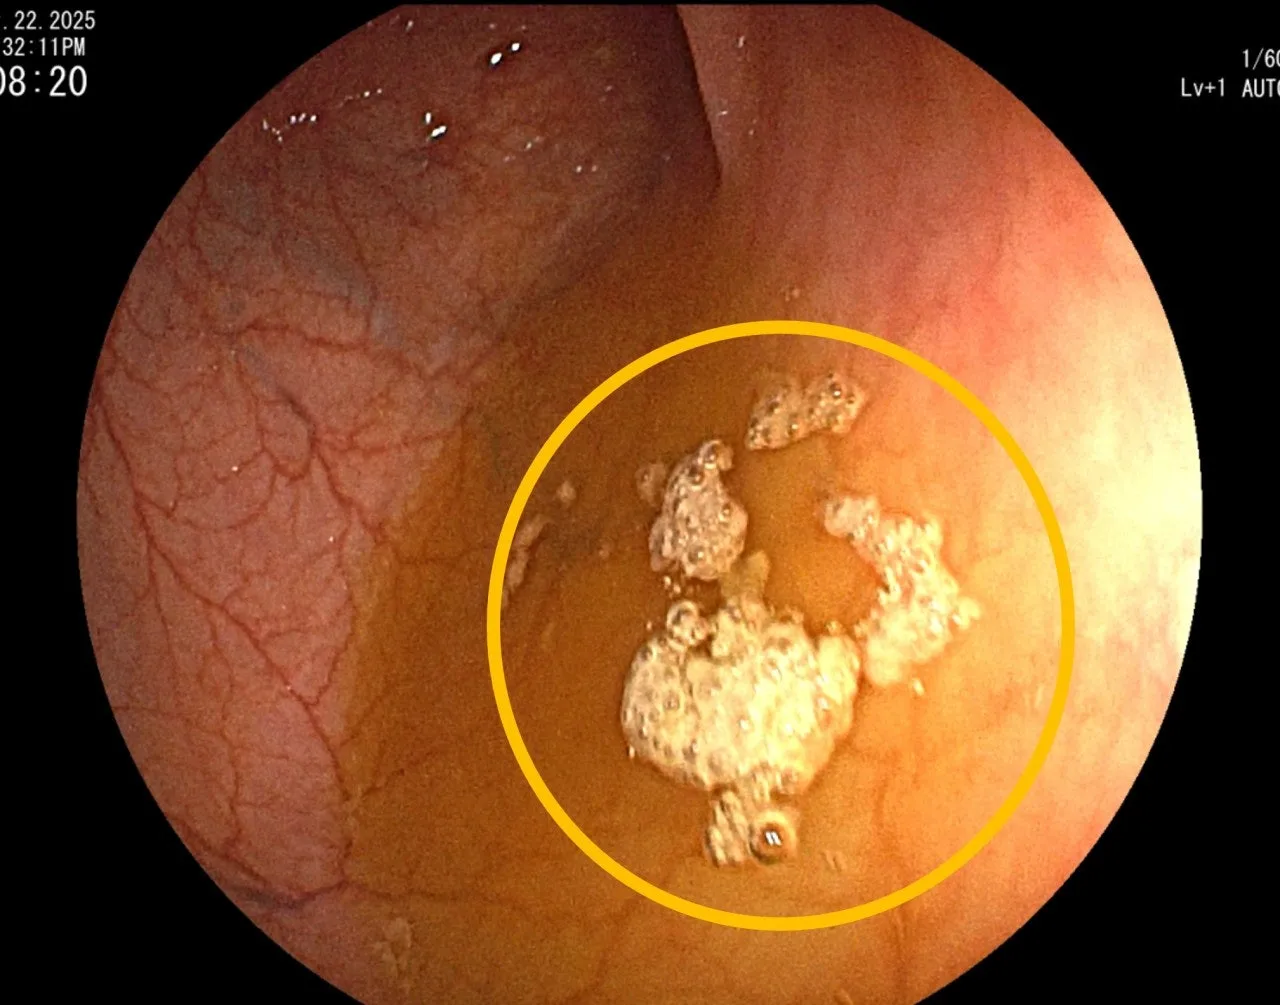

“그럼 저 밑에 저 검은 건(파란색 동그라미) 뭔가요?”

“네? 저거요? 저건 위 속에 있는 공기입니다.”